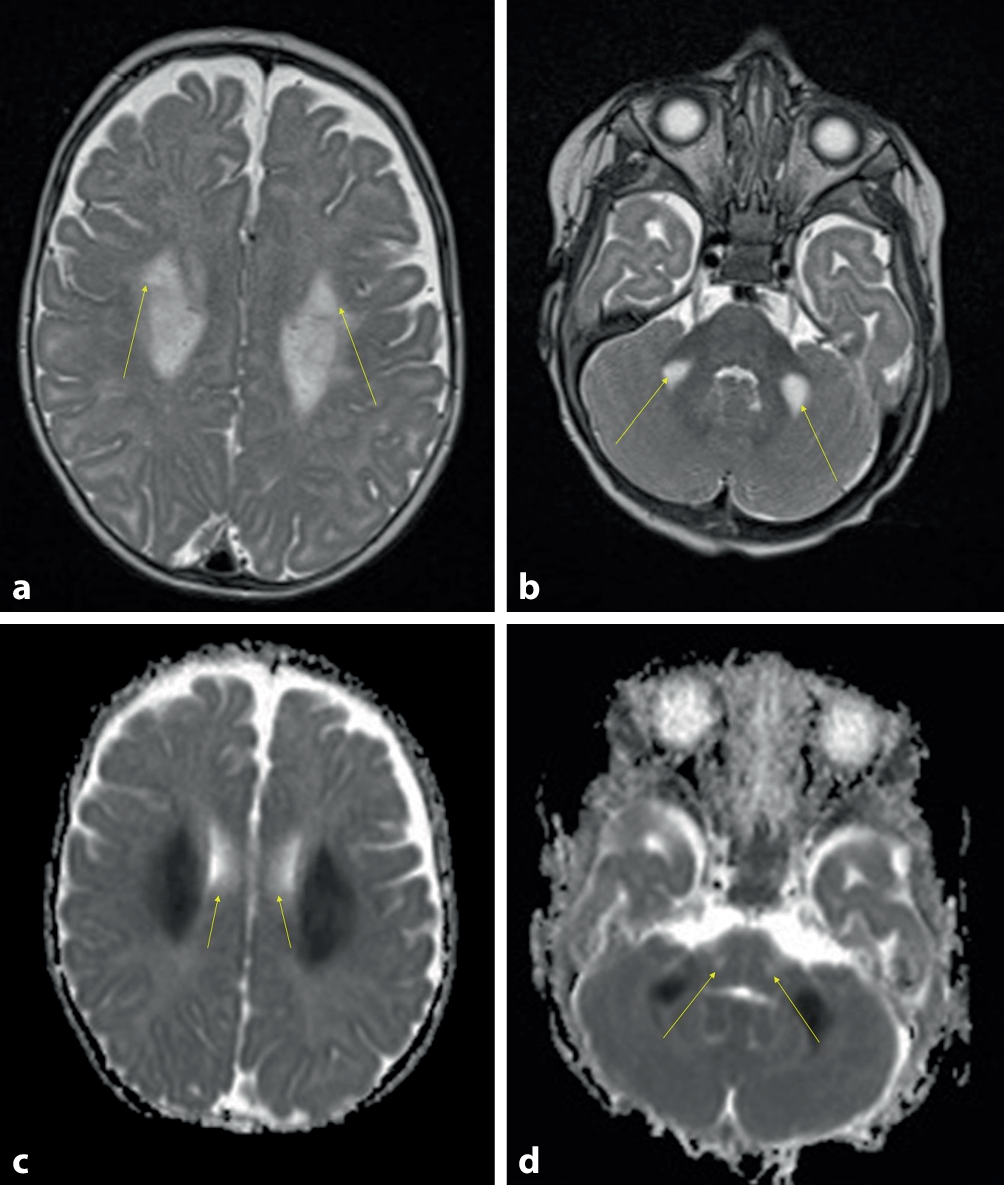

Abb. 2 (korrigierte Fassung)

Zerebrales MRT (axiale T2w, axiale „ADC maps“) bei dem Patienten im Alter von 6 Monaten: a bilaterale symmetrische Signalalterationen der weißen Substanz im Bereich der Corona radiata (aPfeile) und an der Basis des mittleren Kleinhirnstiels (bPfeile). cd Die Signalalterationen weisen eine Diffusionsrestriktion auf (Pfeile)

Bild vergrößern